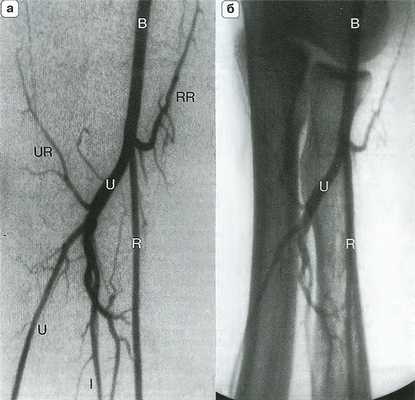

Рис. 14.4. Артериальная анатомия (а) и костные ориентиры (б) локтевого сустава. Плечевая артерия (В) делится на уровне локтевого сустава на лучевую (R) и локтевую (U) артерии. Межкостная артерия (I) является ветвью локтевой артерии, которая в некоторых случаях продолжается на кисть. RR - лучевая возвратная артерия; UR - локтевая возвратная артерия.

Рис. 14.6. Высокое отхождение лучевой артерии. На ангиограмме плеча (а) и предплечья (б) представлен вариант высокого отхождения плечевой артерии (R - стрелки) на уровне средней трети плеча. В - плечевая артерия; I - межкостная артерия; U - лучевая артерия